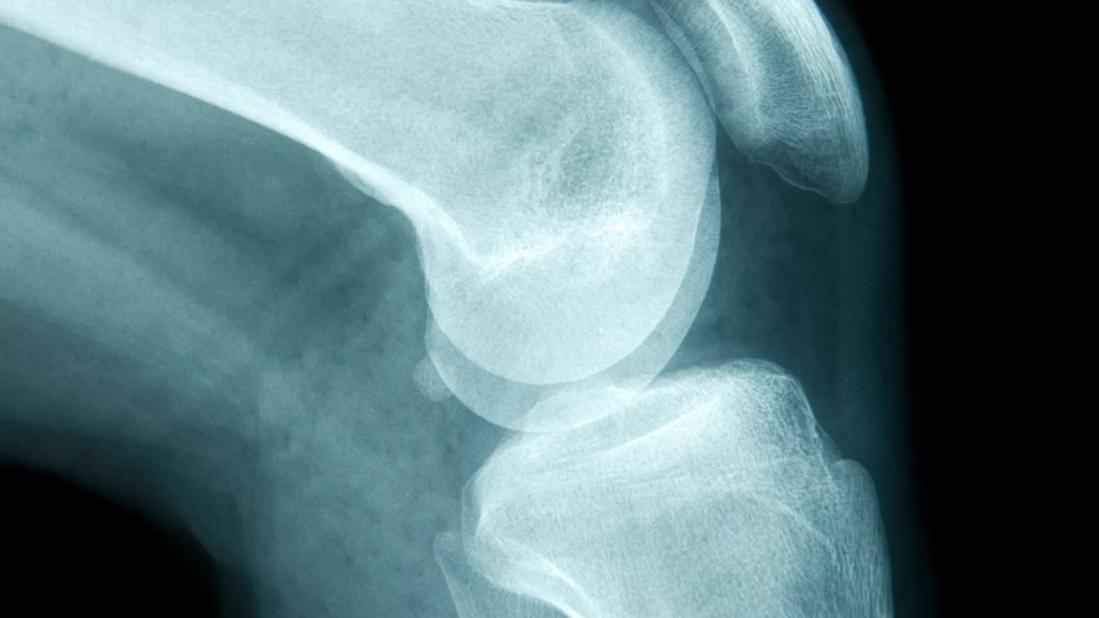

Osteosarcoma is the most common type of bone cancer, and typically develops in the arms or legs. Symptoms can include bone pain, a lump or swelling, and a bone that breaks easily. Experts estimate that fewer than 1,000 people in the U.S. develop osteosarcoma each year. Around 7 in 10 people survive if the disease doesn’t spread to other parts of the body, but only 2 in 10 children survive if the disease does spread outside the original bone site.